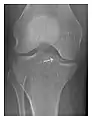

Occult osseous injuries may result from a direct blow to the bone by compressive forces of adjacent bones against one another or by traction forces during an avulsion injury. Lesions in the tibial plateau, hip, ankle, and wrist are often missed. In a tibial plateau fracture, any disruption of the posterior and anterior cortical rims of the plateau should be sought. Impaction of subchondral bone will appear as an increased sclerosis of the subchondral bone (Figure 1). In the hip, posterior acetabular fractures also present subtle radiographic findings. The acetabular lines should then be carefully examined keeping in mind that the posterior rim, which is harder to see on X-rays, is more frequently fractured than the anterior rim (Figure 2). In the wrist, detection of carpal bone fractures is often challenging, with up to 18% of scaphoid fractures radiographically occult. Carpal fractures, especially the scaphoid, are associated with the risk of avascular necrosis. In apparently normal wrist radiographs from symptomatic patients, if there is history of a fall on an outstretched hand with pain in the anatomic snuffbox, suggesting scaphoid injury, the initial examination with posteroanterior, lateral, and pronation oblique views must be complemented by other specific views such as supination oblique and the "scaphoid" view A careful examination of cortices for evidence of discontinuity or offset and cancellous bone for lucency is necessary (Figure 3).[1]

Figure 3: A 26-year-old man presenting with wrist pain after being assaulted. (a) Initial anteroposterior radiograph shows a subtle linear lucency within the scaphoid extending to the scaphocapitate articular surface that was overlooked (arrow). (b) Initial "scaphoid" view was negative. (c) Followup anteroposterior radiographs, 12 days later, shows obvious scaphoid fracture (arrows).[1]